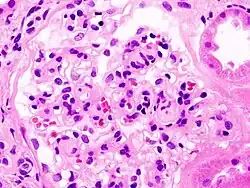

_HE.jpg)

Diabetic kidney disease (DKD) (or diabetic nephropathy) is a progressive microalbuminuria disease with a slight loss of albumin in the urine (30–300 mg per day); DKD has been viewed as a diabetic complication-related microvascular disorder in a renal manifestation.[23] In kidney biopsy, DKD is characterized by glomerular and tubular basement thickening, mesangial expansion, glomerulosclerosis, podocyte effacement and nephron loss.[24] DKD occurs in 30%-50% of the diabetic patient population and leads to kidney failures in up to 20% of the type 1 diabetic patients.[24] However, a substantial portion of DKD patients do not manifest albuminuria.[24] DKD pathogenesis is attributed to the dysregulated glucose transport at a higher glucose level and the excessive influx of intracellular glucose into endothelial cells.[23] The elevated glucose level is sustained, along with multiple metabolic phenotypes such as excess fatty acids and oxidative stress, as well as shear stresses induced by hypertension and hyperfusion, and can lead to microvascular rarefaction, hypoxia, and maladaptation in glomerular neoangiogenesis.[23]